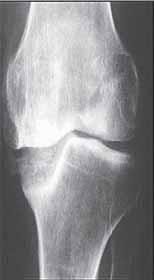

Rycina 14.2. Osteokondukcyjne pobudzenie zrostu kostnego belką i przeszczepami kości allogenicznej złamania okołoprotezowego kości udowej lewej po realoplastyce rewizyjnej stawu kolanowego; a) rentgenogram w projekcji przednio-tylnej (a-p), b) rentgenogram w projekcji bocznej (l).